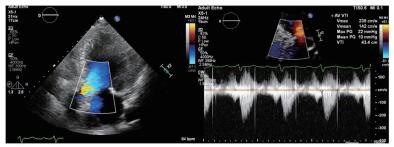

术后随访:患者术后病情稳定,病房继续住院3 d后顺利出院。术后1个月随访化验提示“proBNP 5 869 pg/mL,血肌酐185 μmol/L,肌钙蛋白T 0.118 ng/mL”,复查心超提示“LVEDD 5.19 cm,simpson's测得LVEF 58.6%;主动脉瓣口最大流速2.35 m/s,最大压差22 mmHg,平均压差10 mmHg,瓣口面积1.65 cm2”(图 4)。

| 图 4 患者术后1月随访超声心动图 |